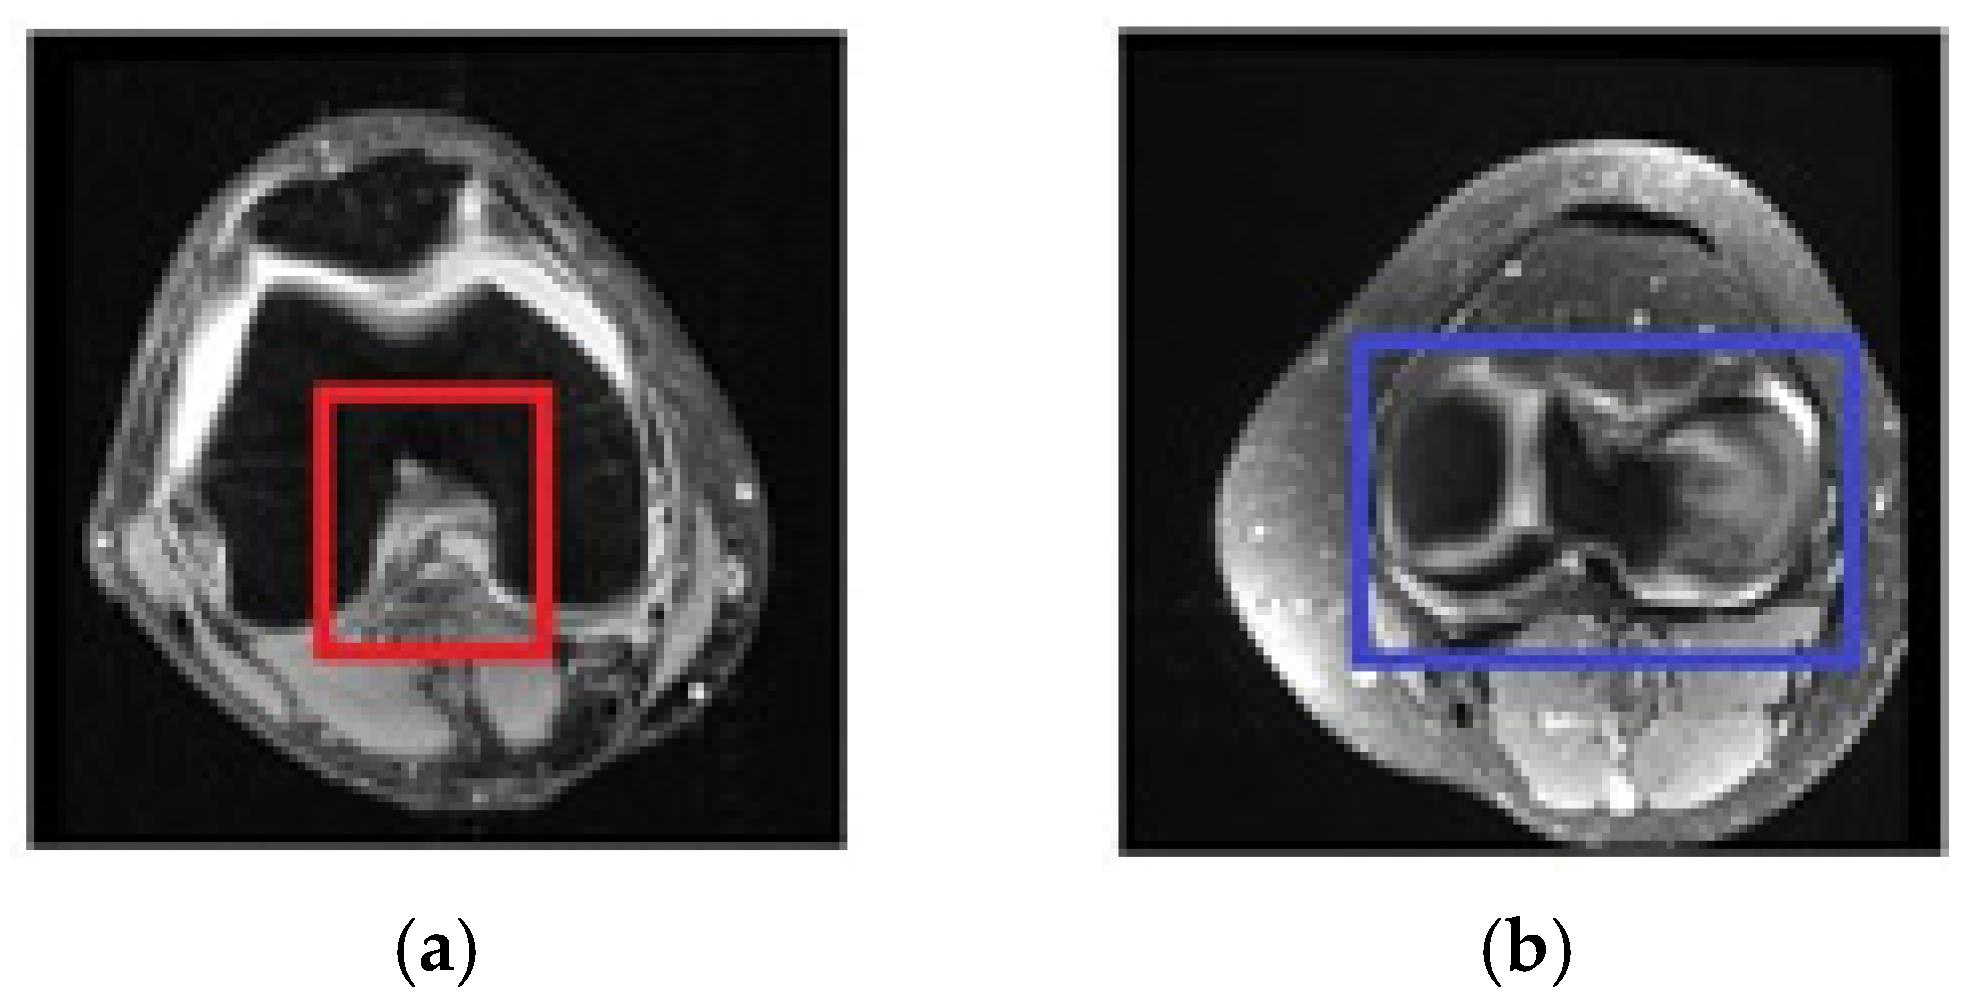

2.4.3. Selecting Relevant Regions on the Axial Axis

2.4.4. Structure of the Region of Interest Model